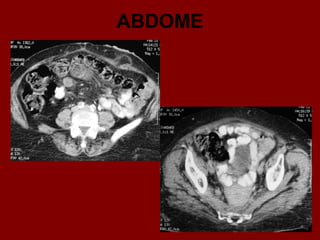

ABDOME